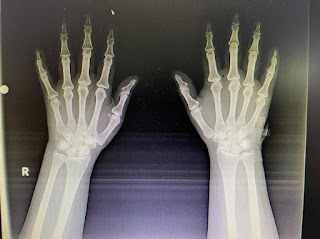

Patient was apparently asymptomatic 12 years back, then she complained of swelling of the uterus, abdominal pain and abnormal uterine bleeding, not subsided even on medication so, hysterectomy was done. Then, 3 years back, she developed fever, bilateral swelling and pain around the joints-(unable to make a fist)( ankle joint, elbow, wrist, small joints in fingers) for 3-4 months in the past 2 years

INVESTIGATIONS: